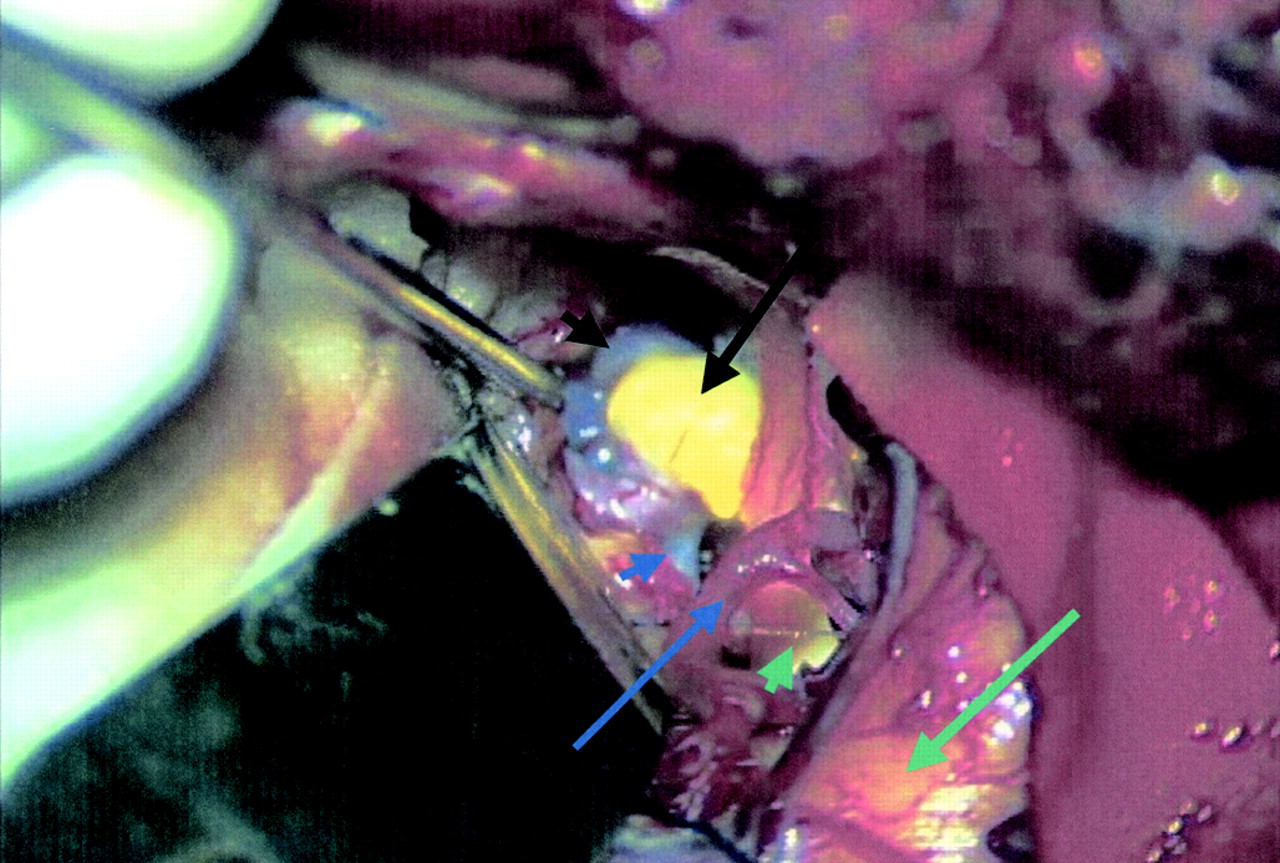

一个10毫米二裂片的前沟通动脉动脉瘤。一个叶包含动脉粥样硬化(黑色箭头),另一个是看到后面(黑色小箭头)。A1段(小蓝色箭头)进入动脉瘤基础。大脑中动脉在前台(蓝色箭头)。正确的视神经也见过(绿色箭头)。颞叶(长绿色箭头被收回),允许可视化动脉瘤的大脑侧裂。